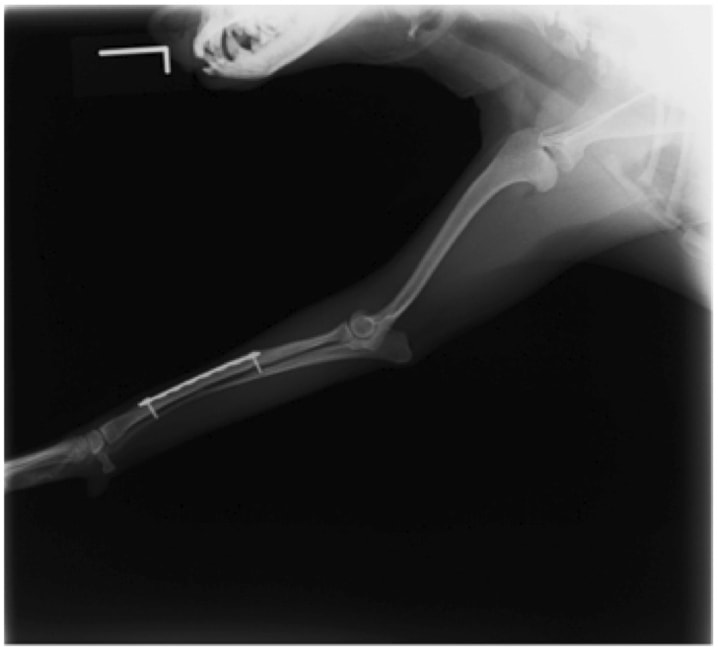

ペルシャ猫 11ヶ月齢 雄

他院にて左大腿骨遠位の成長板骨折(salter-harrisⅠ型)が認められており、治療相談を目的として来院。当院にて、キルシュナーワイヤーを用いたピンニングにより骨折部位の整復を行いました。術後の経過は良好で、現在も経過観察中です。

術前レントゲン